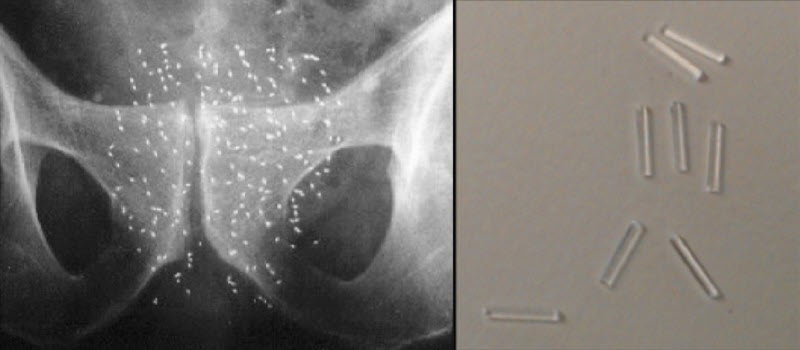

Prostate cancer (PCa) is the second leading cause of cancer related deaths in men with 26,730 deaths and 161,360 new cases estimated in the US in 2017. Treatment options are scarce and often leave survivors with reduced quality of life due to off-target side effects. Radiation treatment in the form of permanent brachytherapy calls for the deposition of radioactive seeds in the prostate gland that release radiation overtime. Standard brachytherapy utilizes plastic inert spacers to obtain spatial guidance to place and separate radioactive seeds. Later stage PCa therapies include highly toxic and aggressive treatments such as systemic chemotherapy to control local progression and spreading of metastasis. Docetaxel (DTX), a chemotoxic agent via mitotic inhibition, is the primary drug used for chemotherapy treatments of PCa. In an effort to combine radiation therapy and chemotherapy to achieve targeted drug delivery and minimize toxicity levels, biodegradable “smart” spacers have been synthesized. These spacers are fabricated with a docetaxel loaded Poly(lactic-co-glycolic) acid (PLGA) cylindrical implant for intratumoral injection during brachytherapy procedures. Previous research has demonstrated the success of such spacers created from a mixture of PLGA, DTX and a solvent. In this project, methods to create solvent-free “smart” spacers are underway and require rheological and calorimetric analysis of the materials. Learned characteristics from these tests will enable us to successfully hot-melt extrude DTX loaded biocompatible spacers to be used in conjunction with radioactive seeds. Further research for this project regarding in vitro experiments and in vivo experiments in rodent models will help determine the synergistic affects of the combined chemo-radiation therapy (CRT) for tumors. The associated benefits of CRT compared to monotherapy require synchronization of the two modalities to achieve maximum benefit. The need to investigate novel PCa therapeutic strategies is immediate and will provide patients with higher survival rates, improve targeted drug delivery and avoid systemic toxicity.